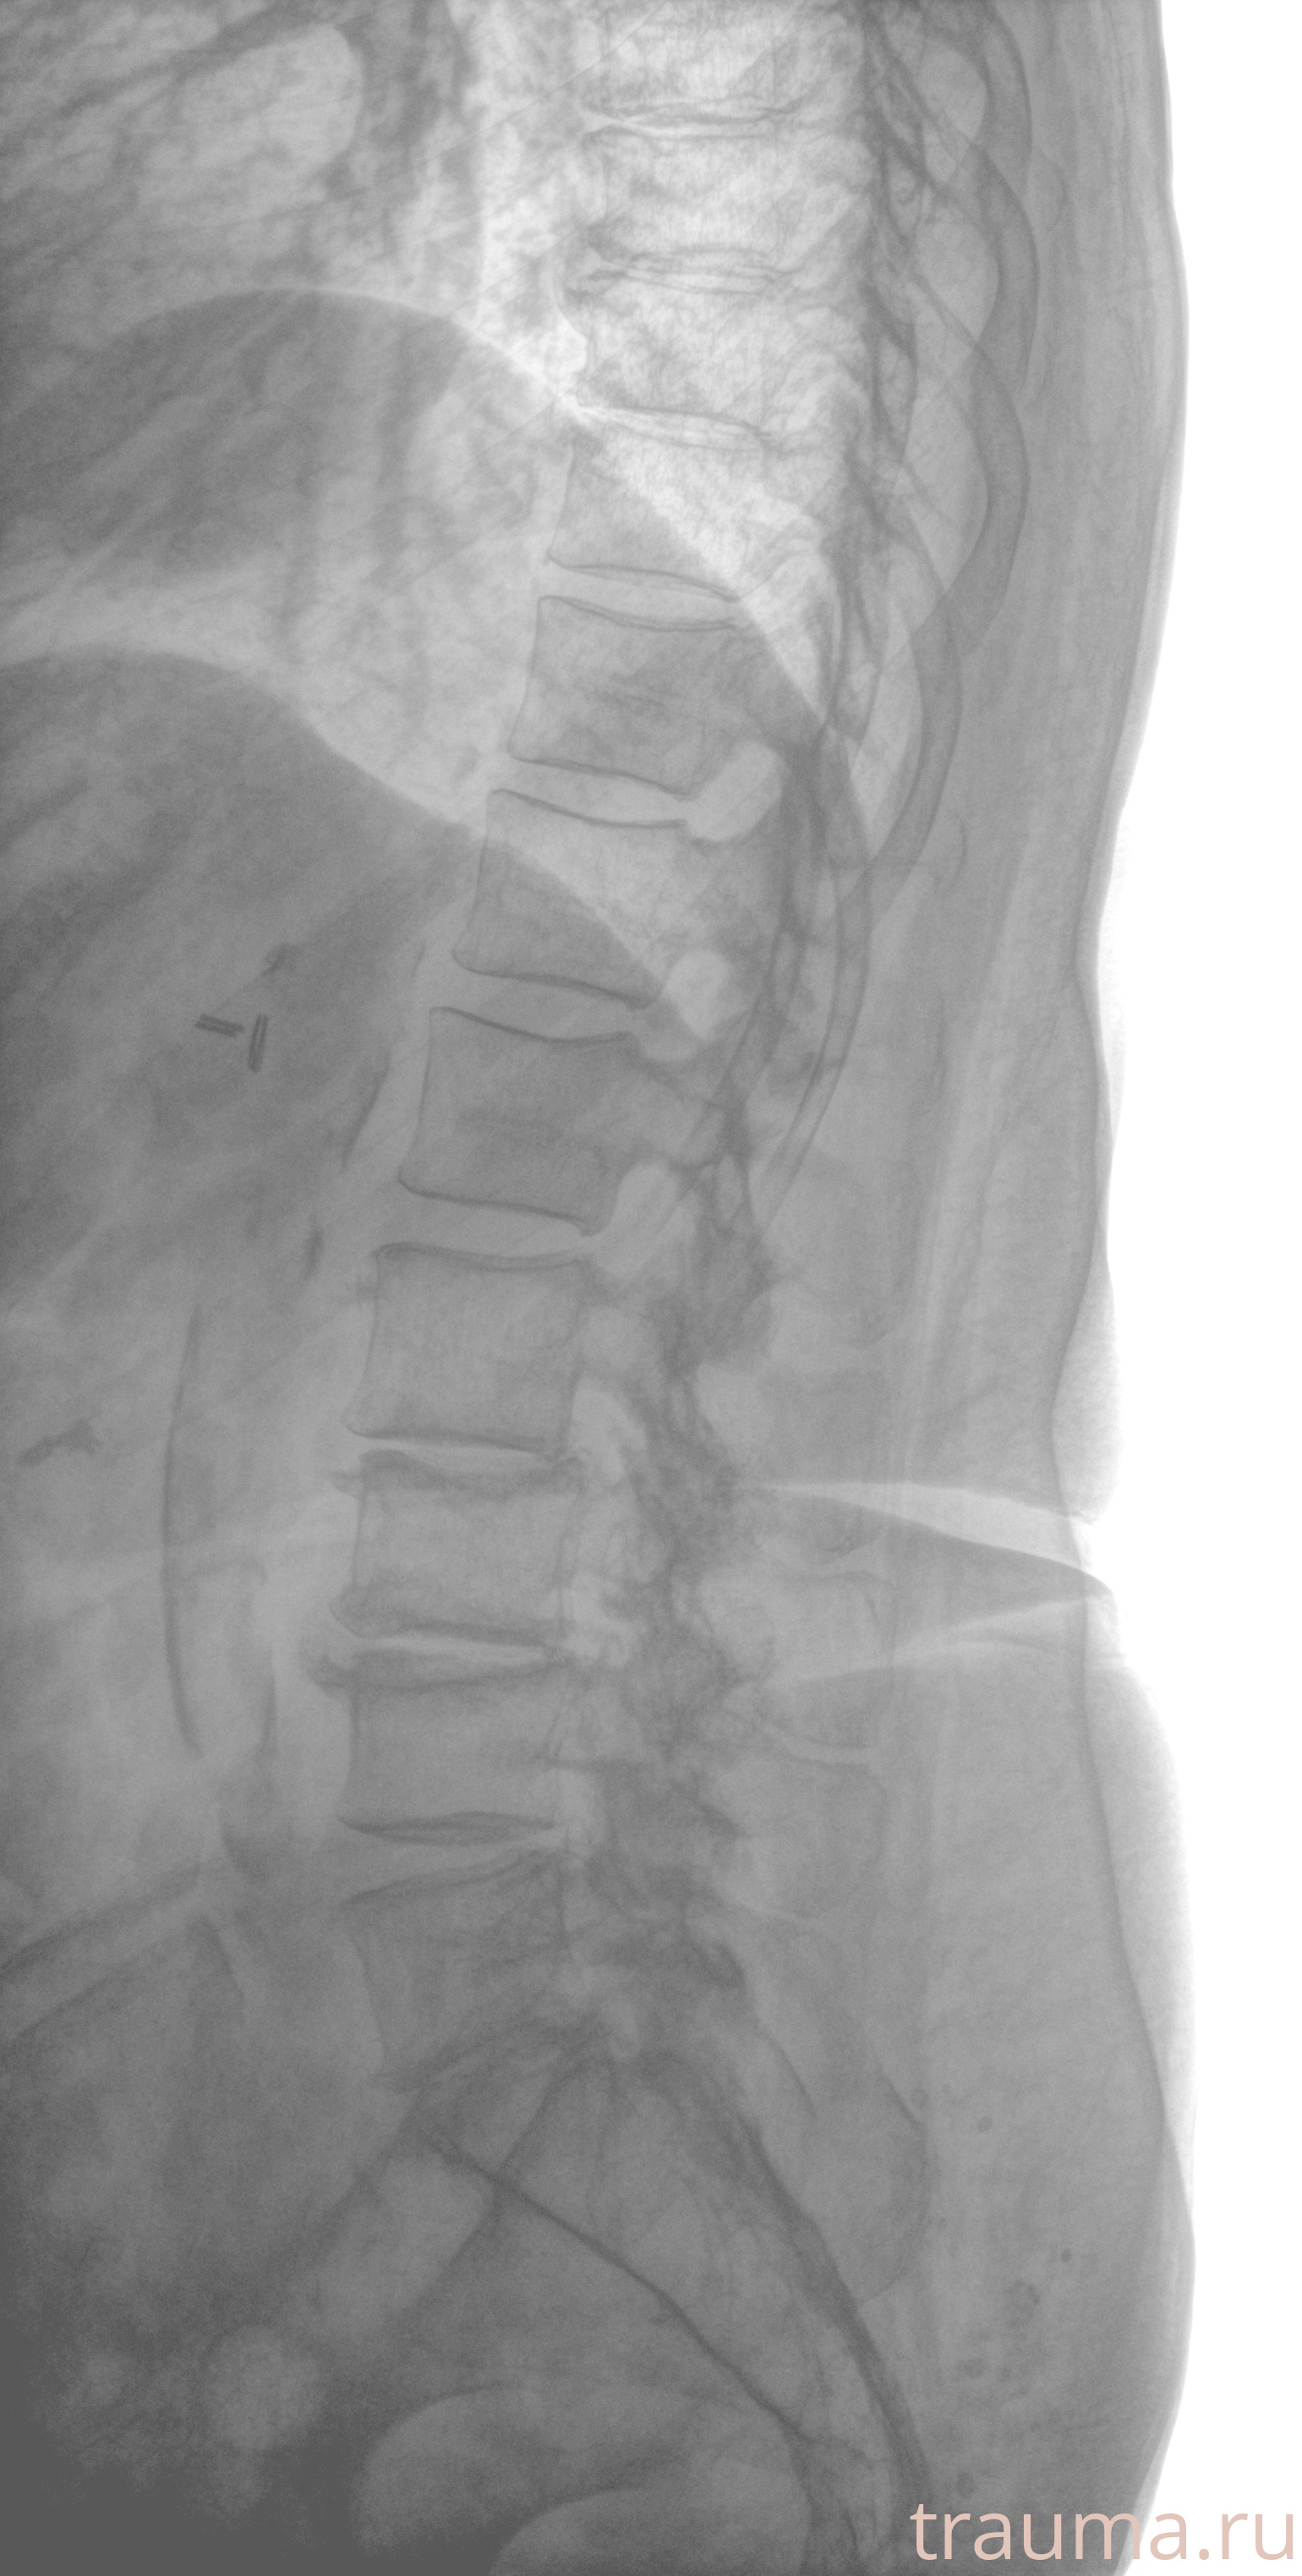

Рентгенограммы

Рентген на дому: по вашему адресу приезжает врач-рентгенолог, травматолог-ортопед с мобильным рентгеновским аппаратом, проводит диагностику травмы или заболевания, делает необходимые рентгенограммы, дает рекомендации по дальнейшему лечению. Получить качественные снимки в домашних условиях возможно благодаря уникальной методике, разработанной МосРентген Центром для института  Склифосовского